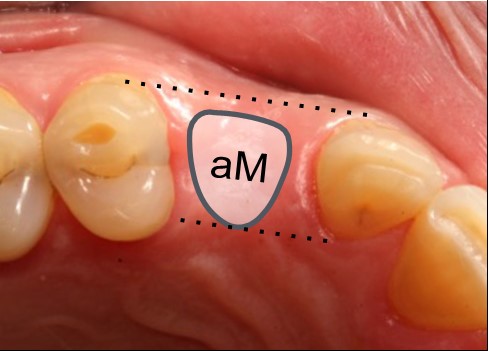

Partea 2 – Identifică dimensiunile și forma profilului cervical gingival ideal (Bont personalizat de vindecare)

Utilizează fila de formă anatomică din același grup ca pentru dintele lipsă (de ex. Premolar).

Poți utiliza alternativ cele trei dimensiuni diferite (mici, medii sau mari) până când identifici dimensiunea potrivită. Mărimea ideală este cea cu aceeași dimensiune buco-linguală cu cea a coroanei care urmează să fie plasată (biotip de țesut moale gros), sau o dimensiune mai mică (biotip de țesut moale subțire).

Pune o notă în diagrama pacientului din fila selectată (de exemplu, pS)

Biotip de țesut moale gros (a)

Biotip de țesut moale gros (a)

Ai ales o dimensiune egală cu cea a porțiunii cervicale a viitoarei proteze.

Biotip de țesut moale subțire (b)

Ai ales o dimensiune mai mică decât cea a porțiunii cervicale a viitoarei proteze.